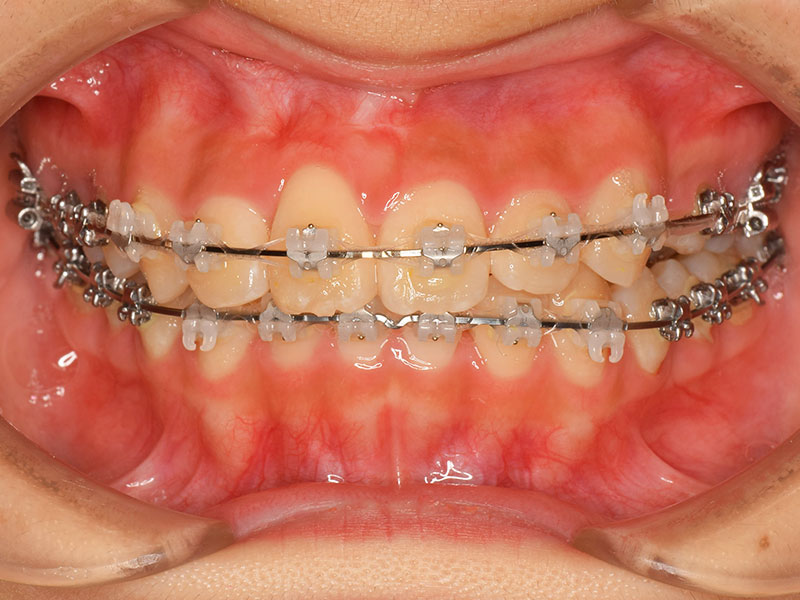

4、ワイヤーセット

奥歯にバンドを作り、ワイヤーを通しますお口の中に装置を全て装着し、歯を抜き終えたらワイヤーをセットします。

矯正治療のスタートです。